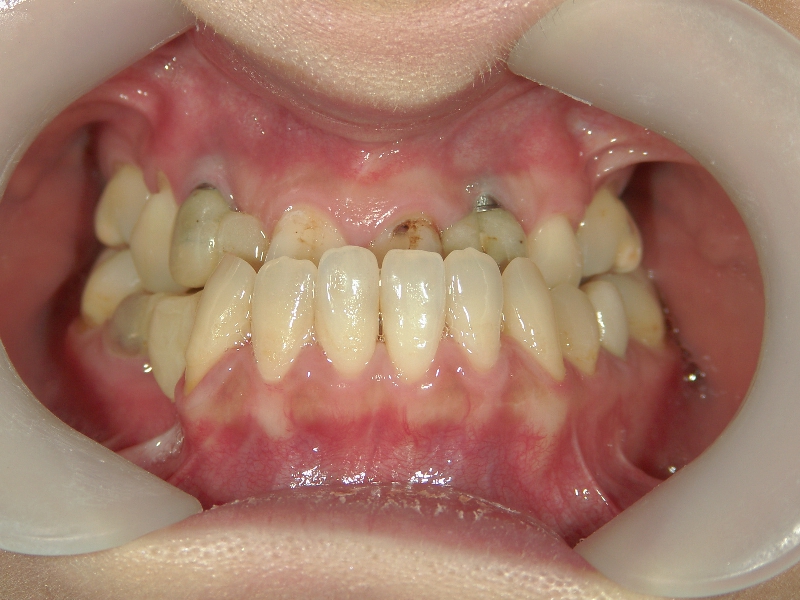

● ツインフォース

下顎が後退している方に用いられる装置です。後ろにずれている下顎を前方(本来の位置)に移動させ、噛み合わせを整えます。

上顎に比べ、下顎が著しく後退しています。

上の歯と下の歯を斜めに繋ぐようにツインフォースという装置を装着します。装置の力で、顎が前方へ押し出されてきました。

顎の移動が終了しました。装置を外して、今後はワイヤーを使用して歯列を治します。

矯正治療後の後戻りを想定して、あえて必要量を越えた顎の移動を行います。